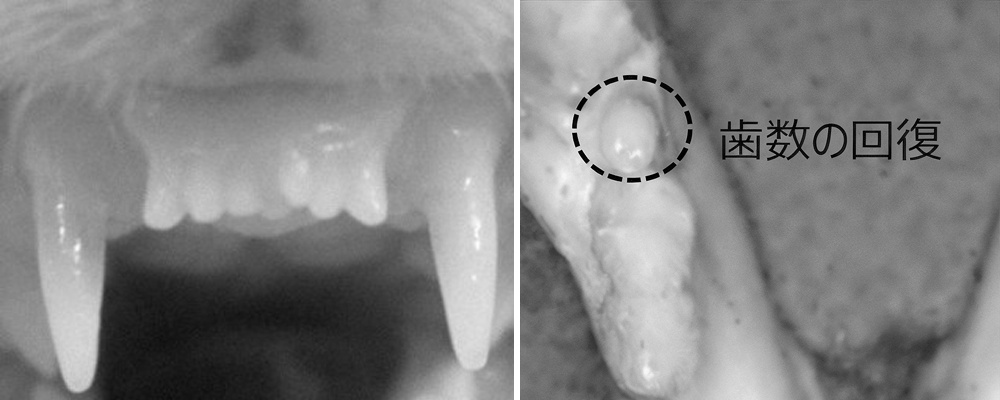

Новые передние зубы хорька (слева) и новый зуб мыши (справа), прошедших лечение препаратом для восстановления зубов

Во время лабораторных исследований на мышах одна инъекция дала полноценные зубы без побочек. Сейчас проходят испытания на 30 взрослых мужчинах с отсутствием хотя бы одного зуба. Далее запланировано дать препарат детям 2–7 лет с врождённой адентией – это когда зубы совсем не закладываются от рождения.